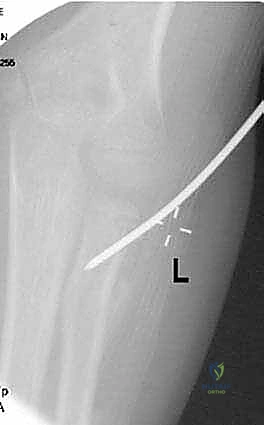

صورة شعاعية توضح كسراً من الدرجة الثالثة يتطلب تدخلاً دقيقاً لإعادة الرأس الكعبري إلى مساره التشريحي.

* يتم استخدام طرف المسمار المنحني كـ "أداة دفع" لرفع رأس الكعبرة المكسور وإعادته إلى مكانه التشريحي الصحيح بدقة متناهية تحت جهاز الأشعة (C-arm).

صورة توضح دخول المسمار المرن عبر التجويف النخاعي لرد الكسر من الداخل دون المساس بمفصل المرفق.